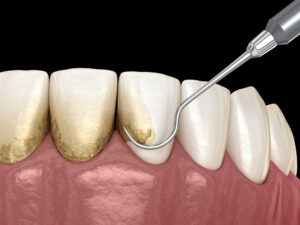

歯石除去

歯石除去は、ザラザラとした歯の表面を滑らかにし、口腔内の健康を保つための基本的な処置です。

歯科医院では、歯石を効率的に取り除く超音波スケーラーと、細部を丁寧に磨き上げる手動スケーラーで歯の表面をしっかりとクリーニングします。

定期的な歯石除去は、歯の表面を滑らかにするだけでなく、歯垢をたまりにくくし、虫歯や歯周病の予防にもつながります。

特に口内トラブルがない場合には、3〜6か月ごとに歯石除去を受けるようにしましょう。